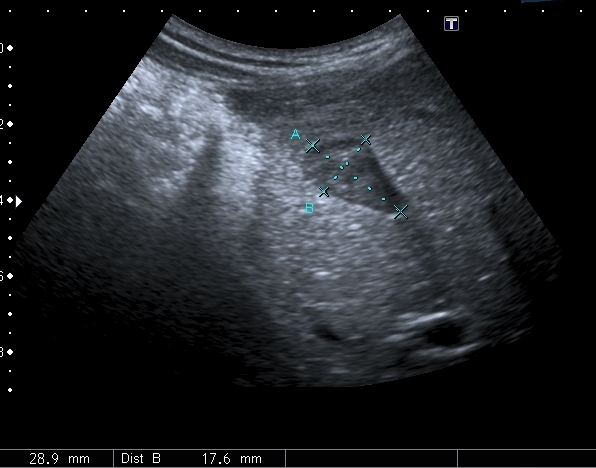

На УЗИ рядом с желчным пузырём определяется овоидное образование солидной струкутры с чёткими контурами.

При ЦДК кровоток в образовании не регистрировался, свободной жидкости в брюшной полости не было.

Полазил в сети на предмет удвоения желчного пузыря. Ультразвуковая картина значительно зависит от уровня, степени удвоения и оттока желчи из удвоенной части желчевыводящей системы. Вероятно в моём случае могло быть фундальное удвоение или V - образный желчный пузырь с нарушением оттока из латеральной половины с общим пузырным протоком. Сосудистый рисунок в печени и её воротах изменён не был. В любом случае хирурги лечить его не собирались - клиники не было. Хотя описаны случаи камнеобразования и опухолей ( почему - то невином) в удвоенном ЖП.Инга писал(а):А что с протоками? Я так предполагаю, что должно быть тоже некое удвоение (р.s я не утверждаю, я предполагаю, я с удвоением ЖП не сталкивалась)